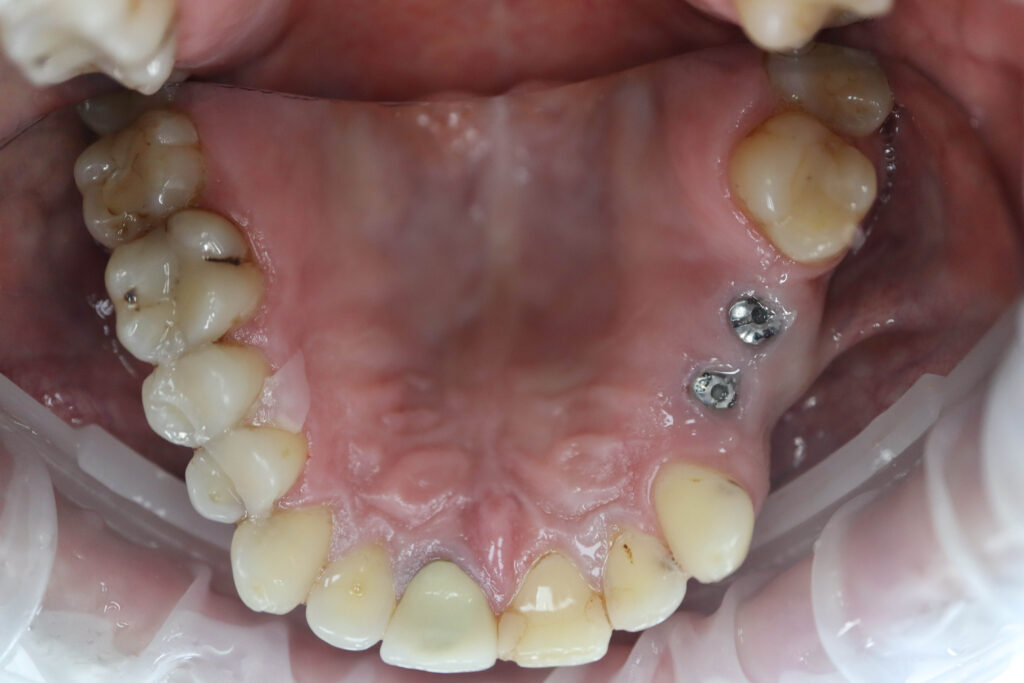

Ситуация до лечения

Пациент обратился с жалобами на эстетические недостатки.

Диагноз: Частичная адентия

Ситуация до лечения Бутримович